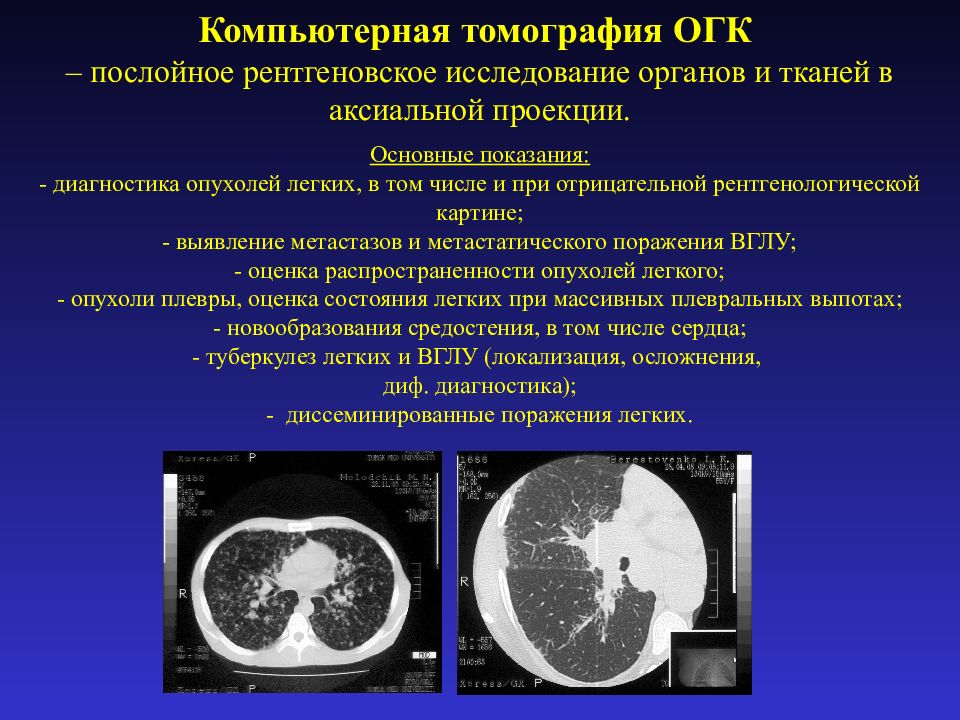

Фотографии и снимки КТ легких без контрастных веществ

Раздел: Визуальный дайджест